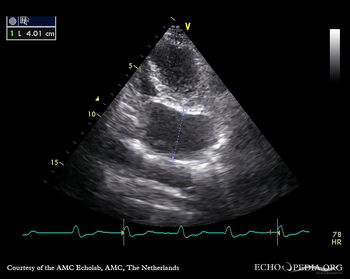

PLAX: dilated coronary sinus A4CH with Color Doppler: severe tricuspid regurgitation